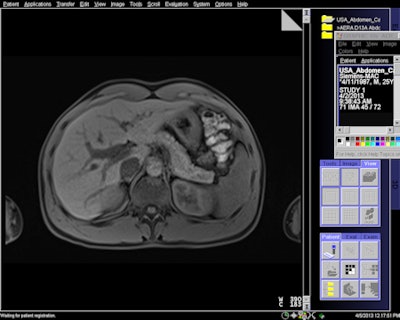

MR image acquired with 7-sec breath-hold with Siemens' CAIPIRINHA software.